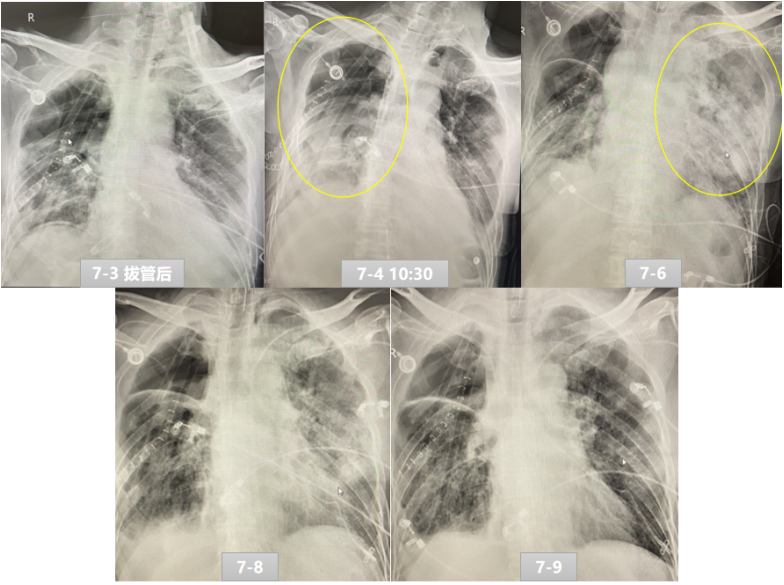

病例:男性,49岁,“颈胸腹三切口食管癌根治术”,术后出现食管胃吻合口瘘,胸腔感染,肺脓肿。右上肺叶切除。7月3日拔管后高流量吸氧,7月4日患者呼吸快,心率快,呼吸窘迫,48 h内再插管。胸片显示:双侧胸水,予以置管引流,右侧肺不张,支气管镜示左主支气管少许暗红色黏痰;右中下肺内见大量暗红色黏液。7月6日胸片见非手术侧(左肺)透光度降低,较前明显进展。7月7日胸部CT见右肺复张不全,左肺炎症渗出伴少量胸水(左侧较前片进展)。而当时EIT监测发现左肺通气良好,但此时患者氧合指数为97 mmHg,血管外肺水指数(ELWI)19 ml/m2,遂予插管及俯卧位通气,同时肌松(顺阿曲库胺)+镇静药物(咪达唑仑)+镇痛(瑞芬太尼)。7月8日俯卧位下,EIT发现右肺通气较前明显改善,左肺通气较前略有好转。此时氧合指数为290 mmHg,ELWI为10 ml/m2。7月9日胸片提示左肺渗出较前减少。7月13日经自主呼吸试验(SBT)顺利拔除口插管,神志清,对答切题。为何患者左肺渗出严重,但左侧通气良好呢?我们分析认为可能患者右肺是手术侧,术后有肺不张,导致其呼吸驱动增加;而左肺作为一个稍正常肺以及术中进行过单肺通气,导致左、右肺的顺应性不一致,在负压性的呼吸驱动过大时,左肺出现了负压性肺水肿。

图片

7月7日EIT

7月8日EIT